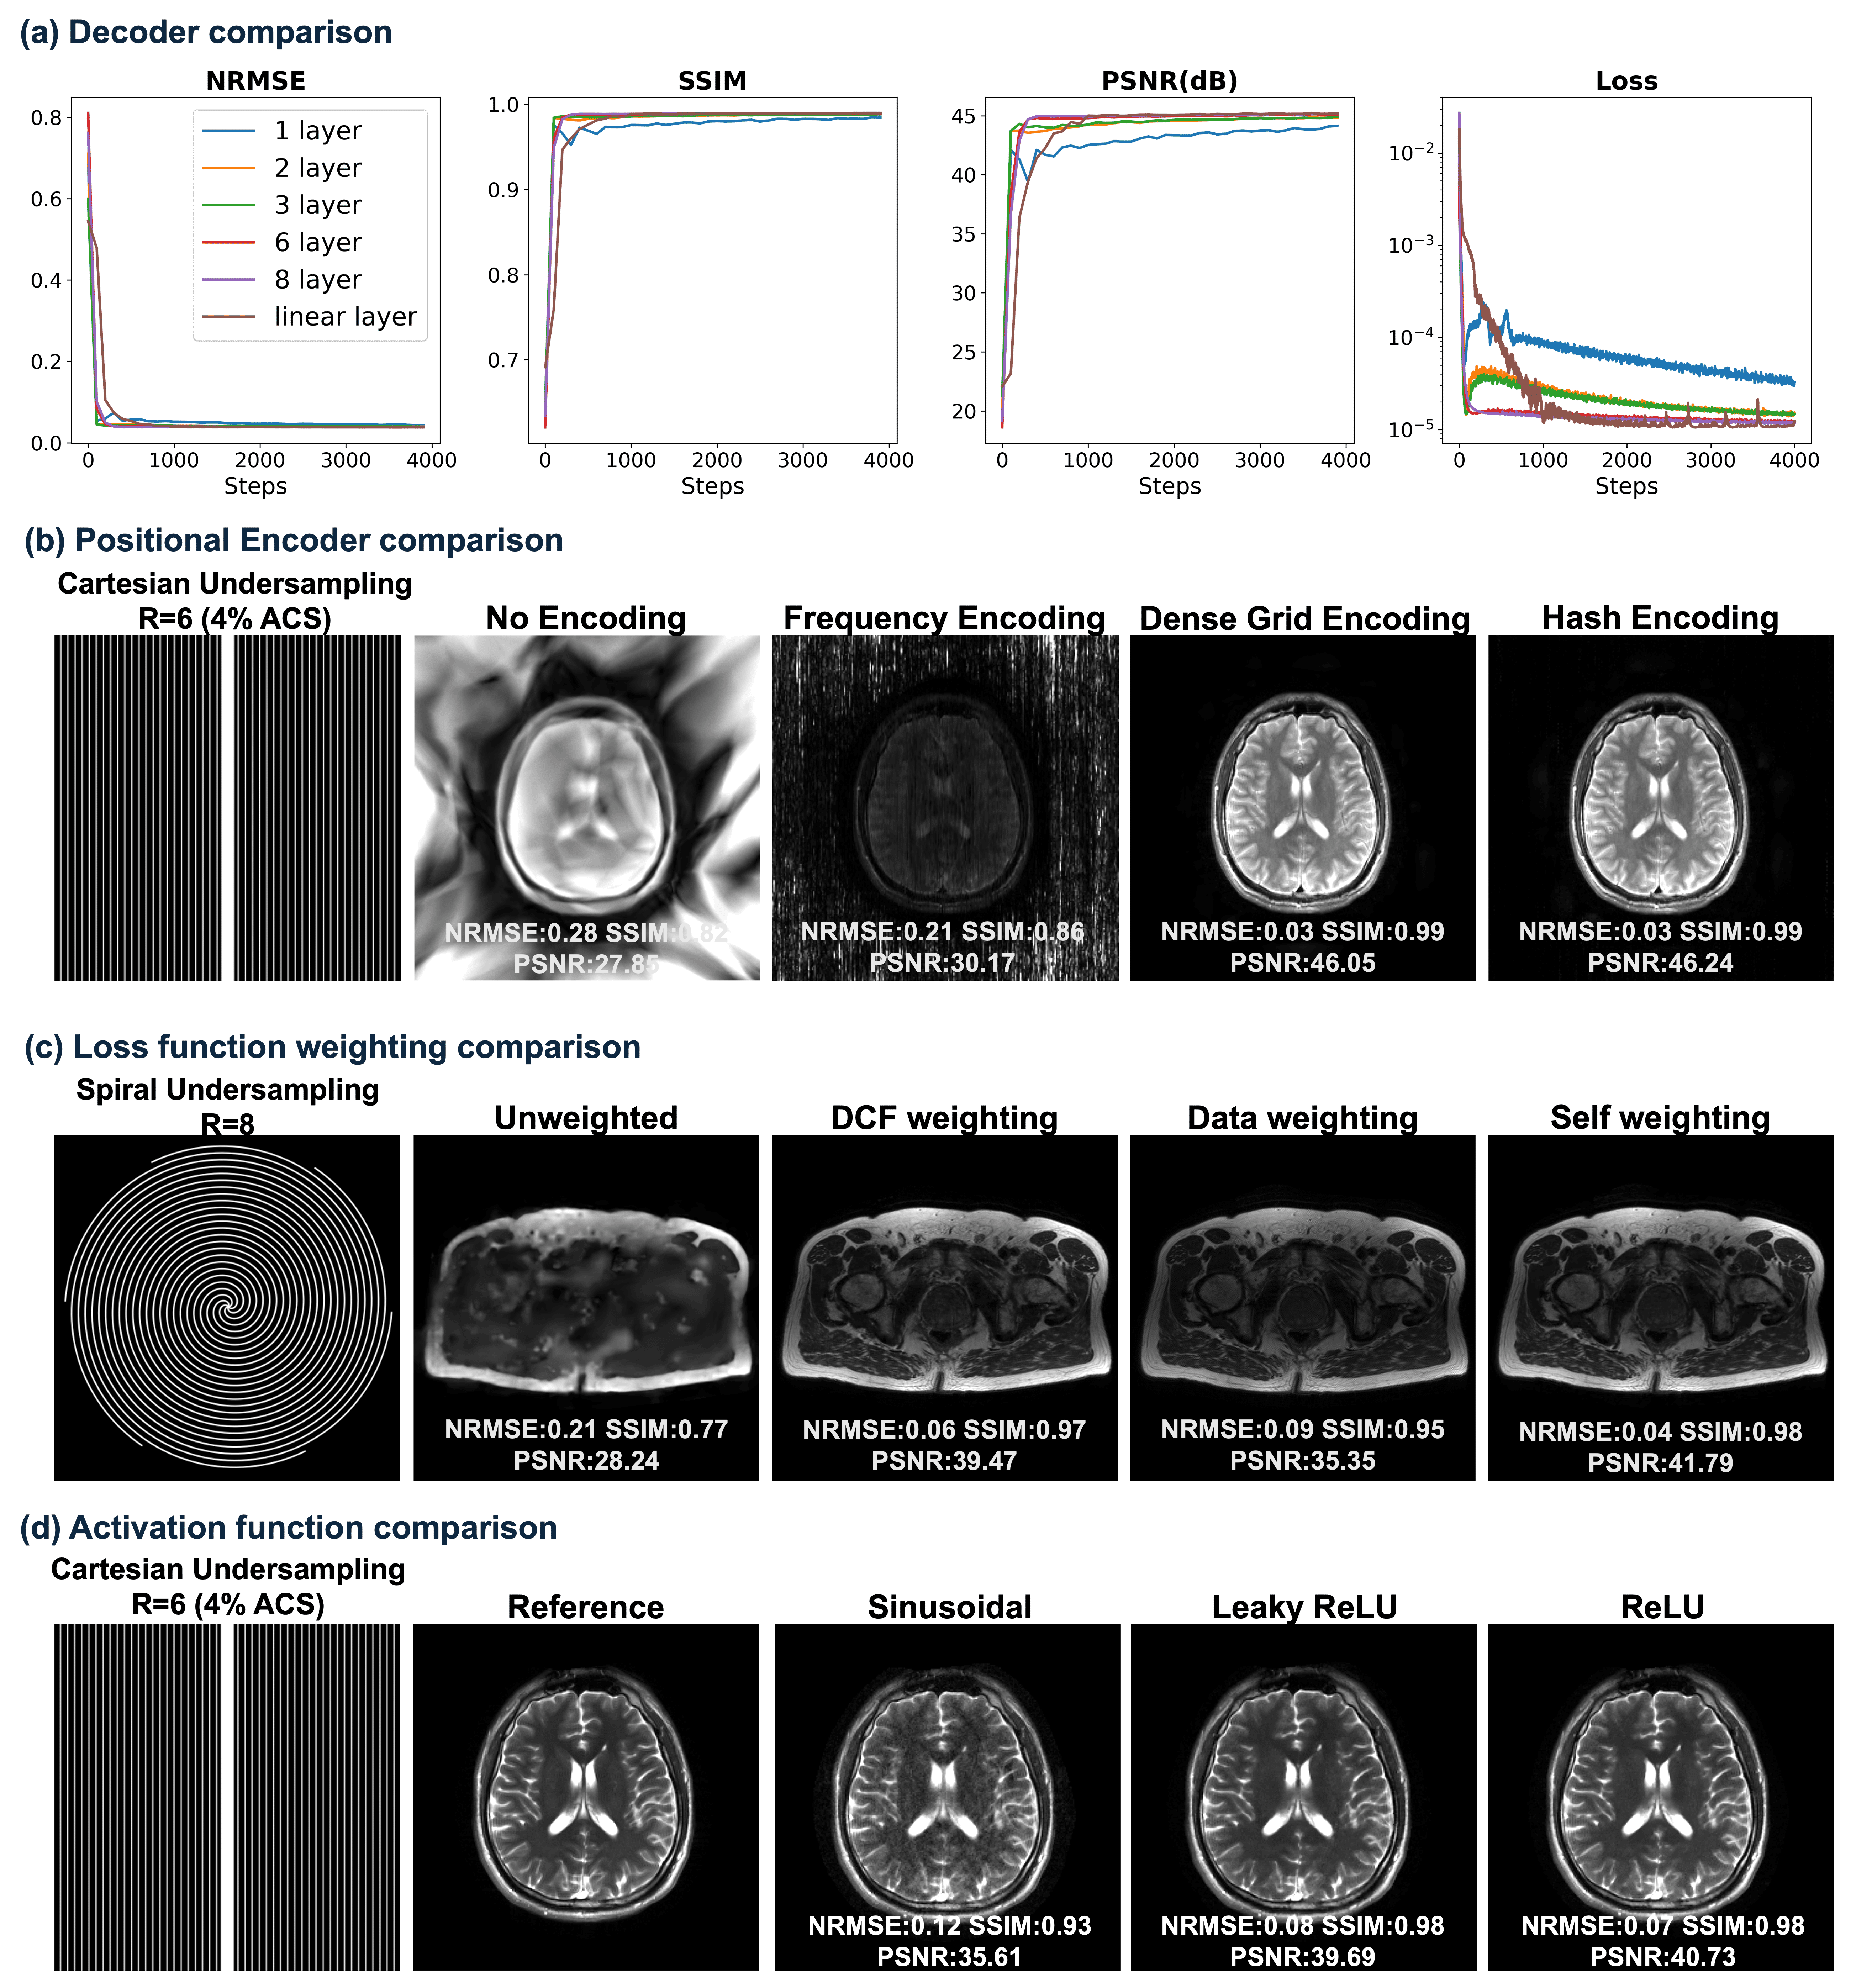

Refer to caption

Figure 3: Method comparisons. (a) Brain volunteer at 3T using bSSFP of 1×1mm21\times 1\ \textrm{mm}^{2} resolution. (b) Brain volunteer at 3T using T2w TSE of 1×1mm21\times 1\ \textrm{mm}^{2} (c) Cardiac volunteer at 0.55T using T2w bSSFP of 1.4×1.4mm21.4\times 1.4\ \textrm{mm}^{2} resolution. (d) Prostate volunteer at 3T using T2w TSE of 1×1mm21\times 1\ \textrm{mm}^{2} resolution. Detailed acquisition protocols are shown in Table 1.

Fig. 3 compares our proposed approach with other model-based iterative and self-supervised deep-learning methods.

For 8×8\times Cartesian undersampled bSSFP brain experiments (Fig. 3(a)), CG-SENSE introduces notable noise across the brain, and 1\ell_{1}-Wavelet, P-LORAKS, and IMJENSE exhibit residual artifacts from the sampling pattern. In contrast, the proposed method shows only minor residual artifacts and achieves a PSNR more than 5 dB higher than the other approaches.

Fig. 3(b) presents results from 20×20\times Poisson undersampled experiments with a central 10×1010\times 10 pixel auto-calibration region. Both CG-SENSE and P-LORAKS show visible non-structured noise in the whole brain. In contrast, 1\ell_{1}-wavelet, IMJENSE, and the proposed bilevel INR display visually artifact-free reconstructions, with our method outperforming others supported by all metrics. INR-based methods (i.e., IMJENSE and ours) benefit from the relatively uniform sampling pattern, which results in non-structural artifacts. These artifacts are easier to remove by INR, because of its strength in learning continuous and smooth function manifolds.

Fig. 3(c) compares methods on a non-gated cardiac dataset at 0.55T, acquired via a T2-weighted bSSFP sequence. The proposed bilevel INR reduces noise and suppresses most motion artifacts by its implicit regularization on continuity. Other methods either fail to remove noise (CG-SENSE, IMJENSE) or retain motion artifacts (P-LORAKS, IMJENSE). The 1\ell_{1}-Wavelet result appears overly smooth.

Finally, for simulated 8×8\times spiral undersampling (Fig. 3(d)), all model-based methods show spiral undersampling artifacts. Our method achieves better metrics and yields nearly artifact-free reconstructions. IMJENSE is omitted here because it only supports Cartesian sampling patterns.

Figure 4: Ablation study. (a) Decoder comparison with fixed Hash Encoder (i.e., Linear layer vs 1/2/3/6/8 layer MLP). (b) Encoder comparison with fixed Decoder MLP. (c) Loss function weighting comparison. (d) Activation function comparison.

Fig. 4 presents ablation experiments on key components of the bilevel-optimized INR. Fig. 4(a) compares decoders of varying depths against a linear layer under identical hyperparameters. Except for the single-layer MLP, all decoders converge to similar performance based on quantitative metrics. Even a linear layer can decode the positionally encoded features effectively, indicating the encoder’s dominant role in the reconstruction pipeline.

Fig. 4(b) evaluates different positional encoders on a 6×6\times Cartesian undersampled T2-weighted TSE dataset. Without encoding or with frequency encoding, the model struggles to capture fine details in the brain, while dense grid and hash grid encodings yield comparable metrics. However, dense grid requires 20×20\times memory and 15×15\times of training time

Fig. 4(c) focuses on loss-function weighting, tested on a spiral undersampled prostate dataset. The proposed self-weighting scheme in (9) has the best reconstruction quality, capturing correct contrast and detailed structure. No loss weighting causes visible blurriness across the pelvic region. Using Pipe’s density compensation function [43] ranks second, with 0.060.06 NRMSE, 0.970.97 SSIM, and 39.4739.47 dB PSNR compared to 0.040.04, 0.980.98, and 41.7941.79 dB from our approach. Substituting the acquired data for the predicted k-space in each iteration leads to a bad local minimum during training, which shows incorrect contrast and degraded metrics.

Figure 5: Demonstration of hyperparameter optimization using Bayesian Optimization. (a) and (b) show comparisons of bSSFP acquisitions at acceleration factors R=6R=6 and R=8R=8 for volunteer 1. (c) shows comparison of bSSFP acquisition for volunteer 2 at R=6R=6, illustrating that hyperparameters are transferable to a different subject for the same imaging sequence. (d) shows a comparison of a T2w TSE acquisition from volunteer 1 in (a) at R=6R=6, illustrating that different sequences require tailored hyperparameter optimization. Acquisition parameters are provided in Table 1.

Figure 6: Demonstration of hyperparameter transferability. Reconstructions of two slices from a multislice prostate acquisition are shown (6×6\times Cartesian undersampled). Each slice is reconstructed with both its own optimized hyperparameters and those from the other slice, indicating that the optimized hyperparameters are transferable across similar anatomy under the same acquisition.

Fig. 5 illustrates the hyperparameter optimization results. Fig. 5(a) and (b) show that Bayesian optimization yields nearly optimal results compared to the oracle optimization across NRMSE, SSIM, and PSNR for both R=6R=6 and R=8R=8 on volunteer 1. By contrast, empirical tuning leads to residual artifacts near the brain center. The empirically tuned hyperparameters were chosen based on previously successful reconstructions for other sequences and resolutions. Table 2 lists the hyperparameter values in each case. Except for the loss-weighting controller δ\delta, all other hyperparameters differ between R=6R=6 and R=8R=8, indicating that each sampling pattern benefits from a tailored optimization.

Fig. 5(c) displays the reconstruction of the same bSSFP sequence with identical acquisition parameters and similar slice position for volunteer 2. Bayesian optimization achieves performance comparable to oracle optimization across all metrics. The hyperparameters optimized for volunteer 1 adapt well to volunteer 2, with similar NRMSE and SSIM, and only slightly worse PSNR, showing that hyperparameters optimized for bilevel INR can be transferred between similar acquisitions.

Fig. 5(d) uses a T2-weighted TSE scan from volunteer 1 at the same slice position to demonstrate the sequence dependence of INR-based reconstruction. The performance using hyperparameters optimized for the bSSFP scan of volunteer 1 is 5.415.41 dB worse in PSNR and 0.050.05 higher in NRMSE compared to tailored Bayesian Optimization. The resulting images appear more blurry because bSSFP sequences generally have lower SNR than TSE, and optimizing for bSSFP tends toward stronger denoising (e.g., λEnc=2.6e4\lambda_{\mathrm{Enc}}=2.6e-4 in (a)). In contrast, T2-weighted TSE scans keep anatomical structures more clearly and thus need less regularization (e.g., λEnc=1.2e5\lambda_{\mathrm{Enc}}=1.2e-5 in (d)) .

Fig. 6 further demonstrates the transferability of hyperparameters across anatomically similar regions. Reconstructions for two 6×6\times undersampled pelvic slices are compared using both tailored hyperparameters (optimized specifically for each slice) and hyperparameters transferred from the other slice. The transferred hyperparameters yield good reconstructions, with only small decreases in PSNR (0.41 dB and 0.58 dB, respectively) compared to the tailored results.